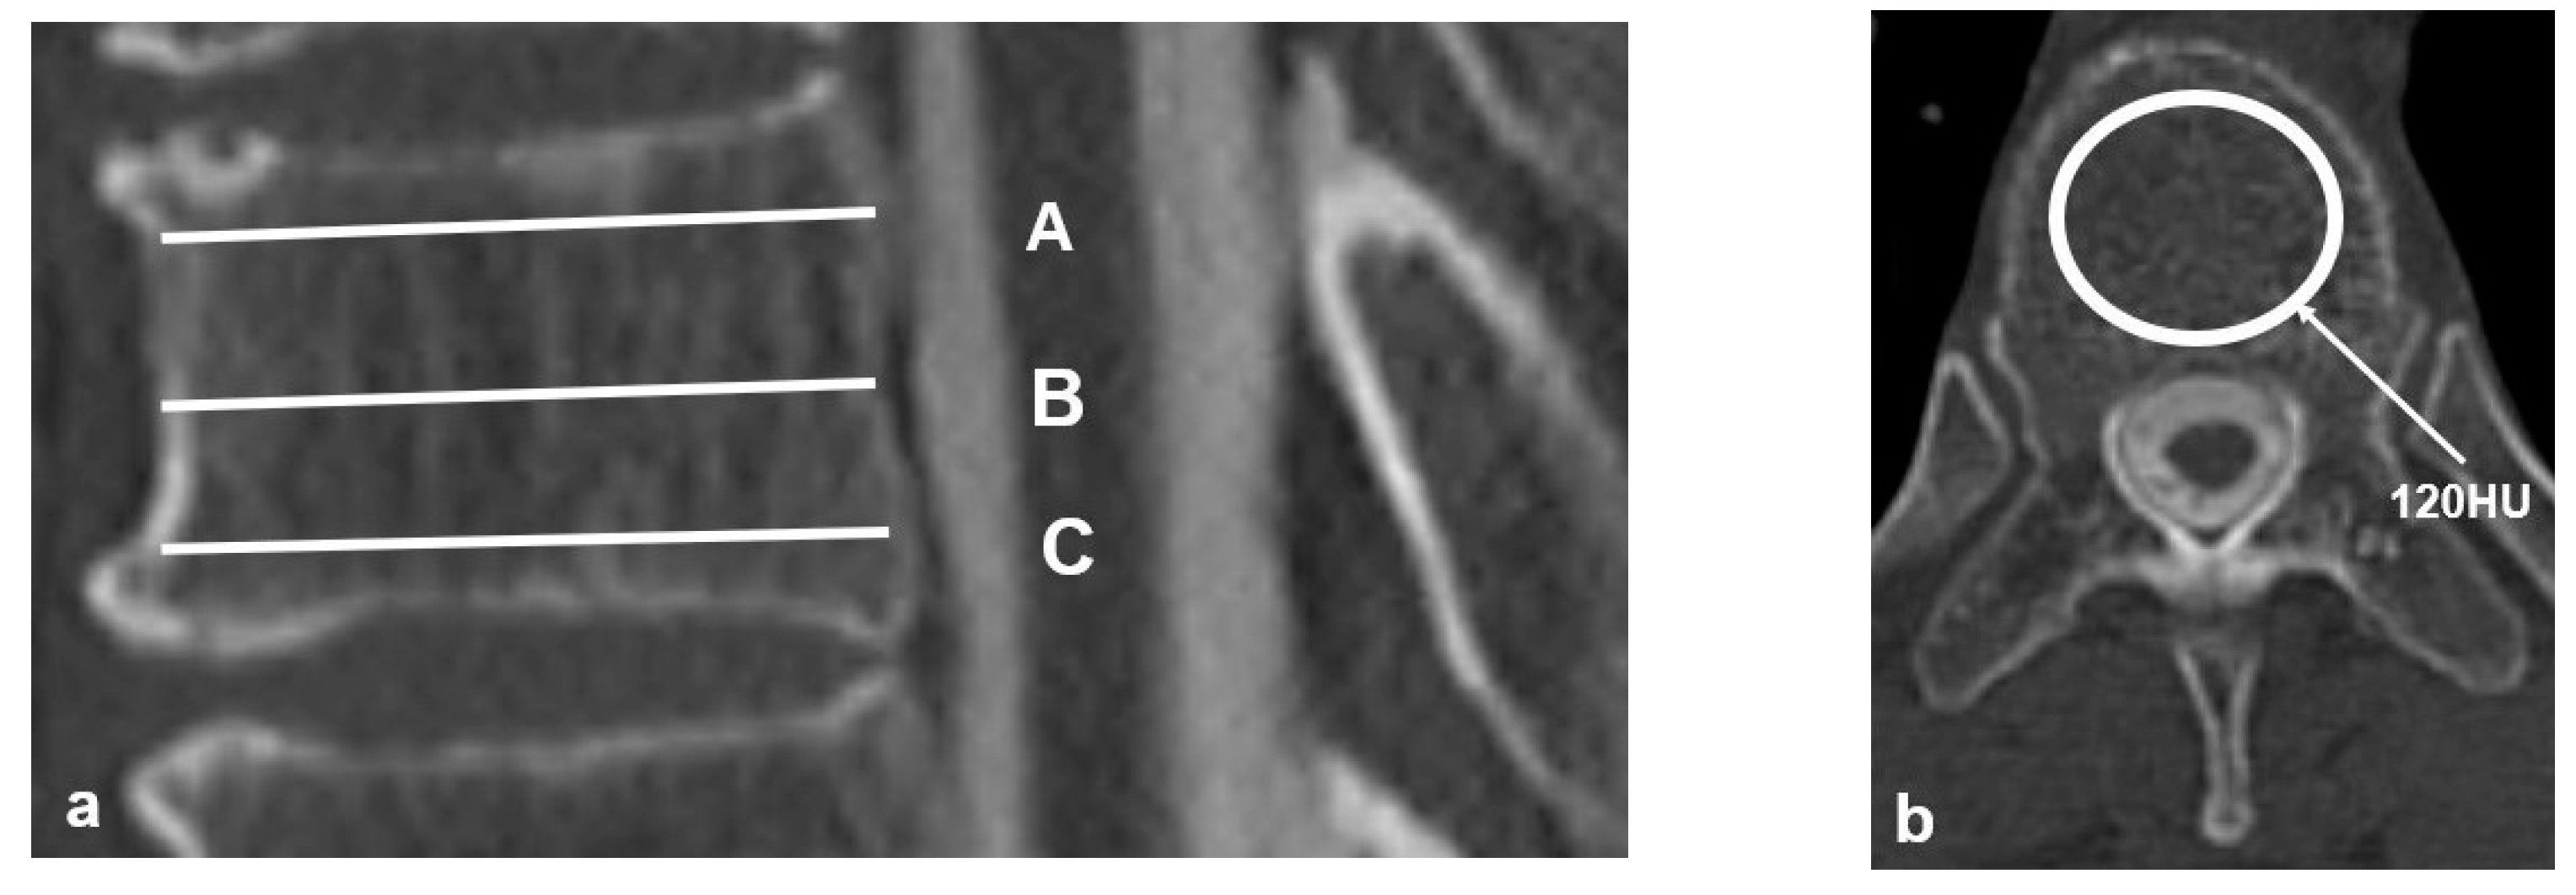

| HU value of the UIV, mean ± SD | 103.4 ± 22.9 | 149.0 ± 42.6 | <0.001 * |

| HU value of the UIV+1, mean ± SD | 102.0 ± 23.8 | 145.7 ± 43.0 | <0.001 * |